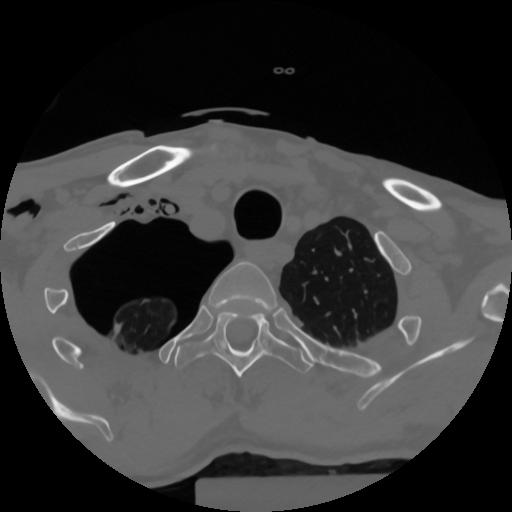

12 P.BLANDAS,,Vol,0.5,P.BLANDAS,,